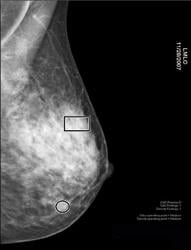

A comparision of a small breast cancer found in a patient without dense breast tissue (left), and a tumor found in a woman with dense fibroglandular tissue. For more information visit DenseBreast-info.org.

Dense breast tissue not only elevates the risk of breast cancer, but also makes it harder to detect mammographically. Cancers, which are white on mammograms, become hidden on a background of dense tissue, which is also white. Whereas the sensitivity of mammography for showing breast cancer is 98 percent for fatty breasts, it drops to only 48 percent for extremely dense breasts. In other words, only half of all breast cancers are visible on mammography when the breasts are dense. Another problem is that women with dense parenchyma are more likely to have breast pain or longer mammography exposure times, both of which can lead to blurry mammograms as a result of patient motion.